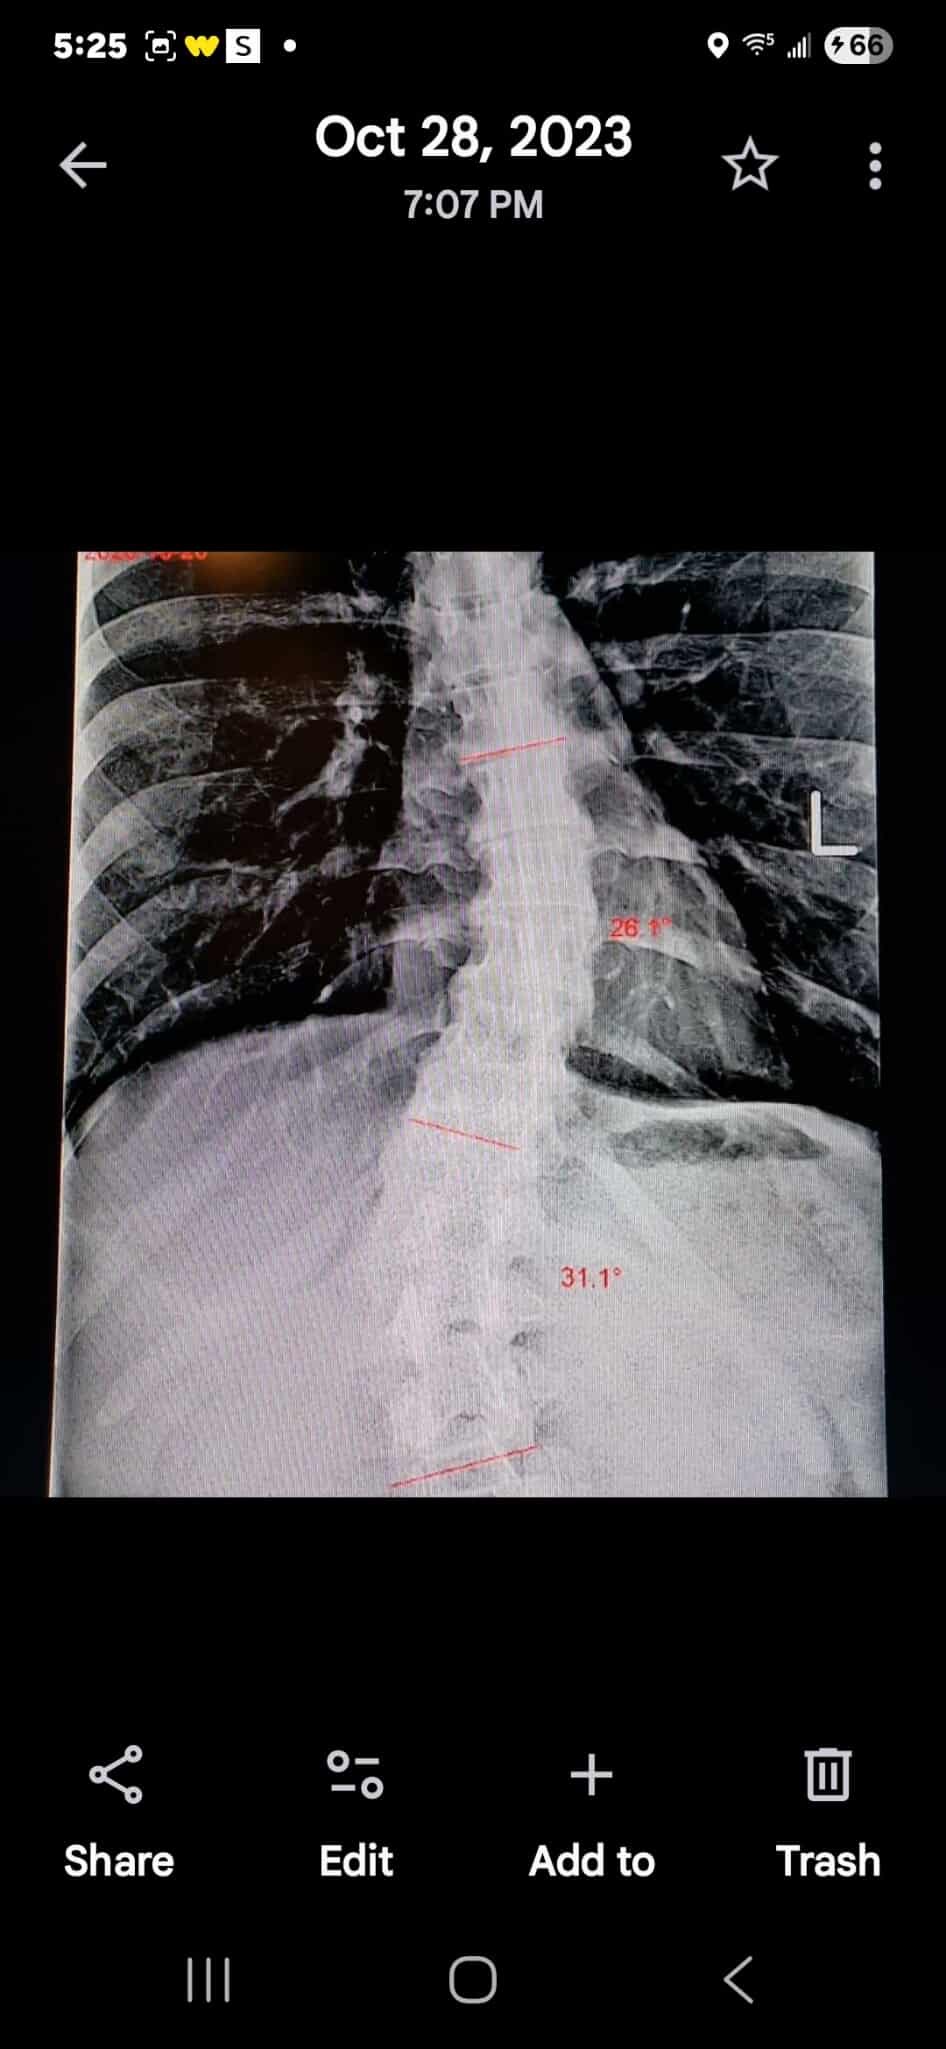

Hi I'm raising money for my friend and former coworker Melissa Brown, a hard worker, talented human being, and loving mother who has been going through a lot this last year. From neck surgery (cervical anterior arthroplasty total disc single level) to diagnoses such as P.O.T.S., E.D.S., M.C.A.S., sleep apnea, hernia, P.C.O.S. and more, there are countless medical bills from appointments, tests, hospitalizations, and medications. The cherry on top? Her health has recently declined to the point she can no longer work unless it's from home.